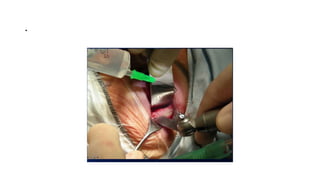

Subbrow incision

Sub brow incision

Subperiosteal orbital abscess